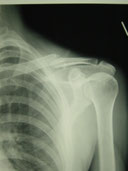

〇右鎖骨骨折

病院で手術の日程が決まっていましたが、保存的治療を希望されので当院で固定と経過観察をしました。(セカンドオピニオンとして整形外科医を紹介し同意)

骨折部位の転位がありますが正しい固定と注意深い経過経過観察、固定時期から積極的に周囲の血行を保つことにより経過良好で完治しました。

数多くの鎖骨骨折を診てきましたが、転位はひどくても正確な固定が維持できれば、かなりの成果があげられます。

今までに偽関節等で再度手術になった方はいらっしゃいません。

ちょうど暑い季節だったので、毎回固定を外し体をボディーソープで清拭しました。持参の下着に着替えてから再固定をしたのでストレスが少なかったと思います。